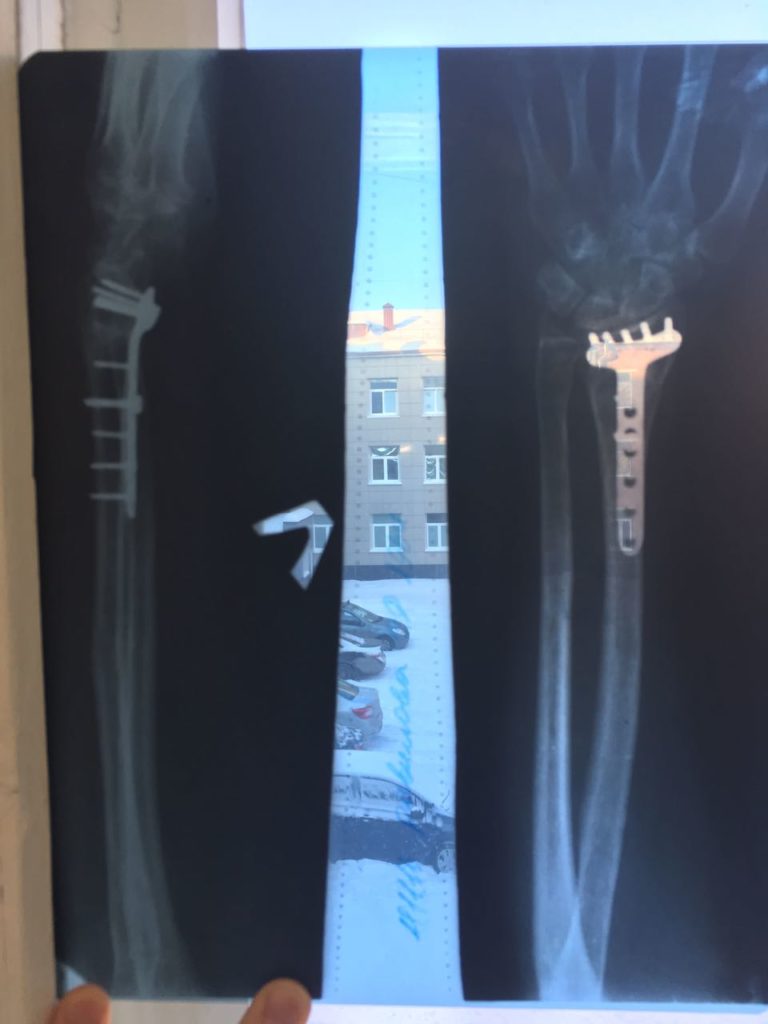

Операция - открытая репозиция, остеосинтез лучевой кости пластиной с костной ксенопластикой материалом "Остеоматрикс". На контрольных снимках в три месяца имеется консолидация перелома, миграции фиксатора нет, имеется остеоинтеграция ксенопластического материала.

Отдаленные результаты через 6 (шесть) месяцев